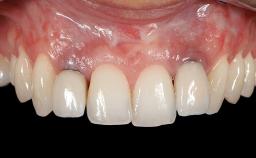

Soft-Tissue Volume Augmentation Using a Connective-Tissue Graft Harvested from the Maxillary Tuberosity